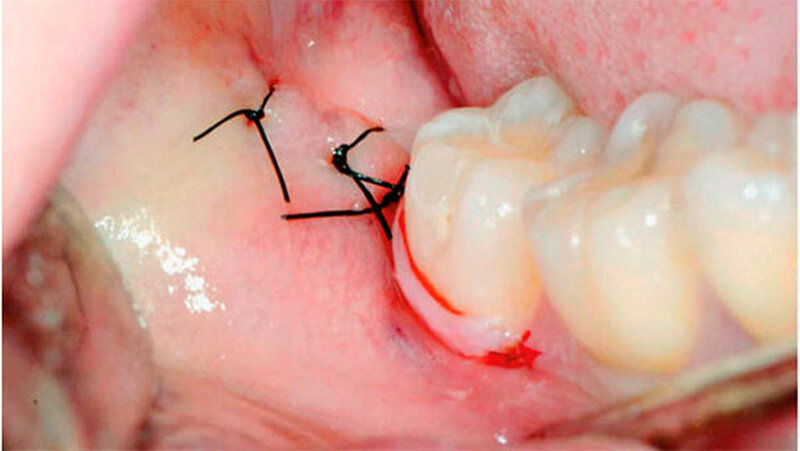

Nach Kürettage und Spülung mit NaCl-Lösung wurde der Lappen reponiert und ein primärer Wundverschluss durchgeführt (Supramid 4–0, B Braun Medical AG, Sempach, Schweiz). Zur Analgesie wurde der Patientin Mefenaminsäure 500 mg (Mefenacid, Streuli Pharma AG, Uznach, Schweiz) dreimal täglich verordnet.